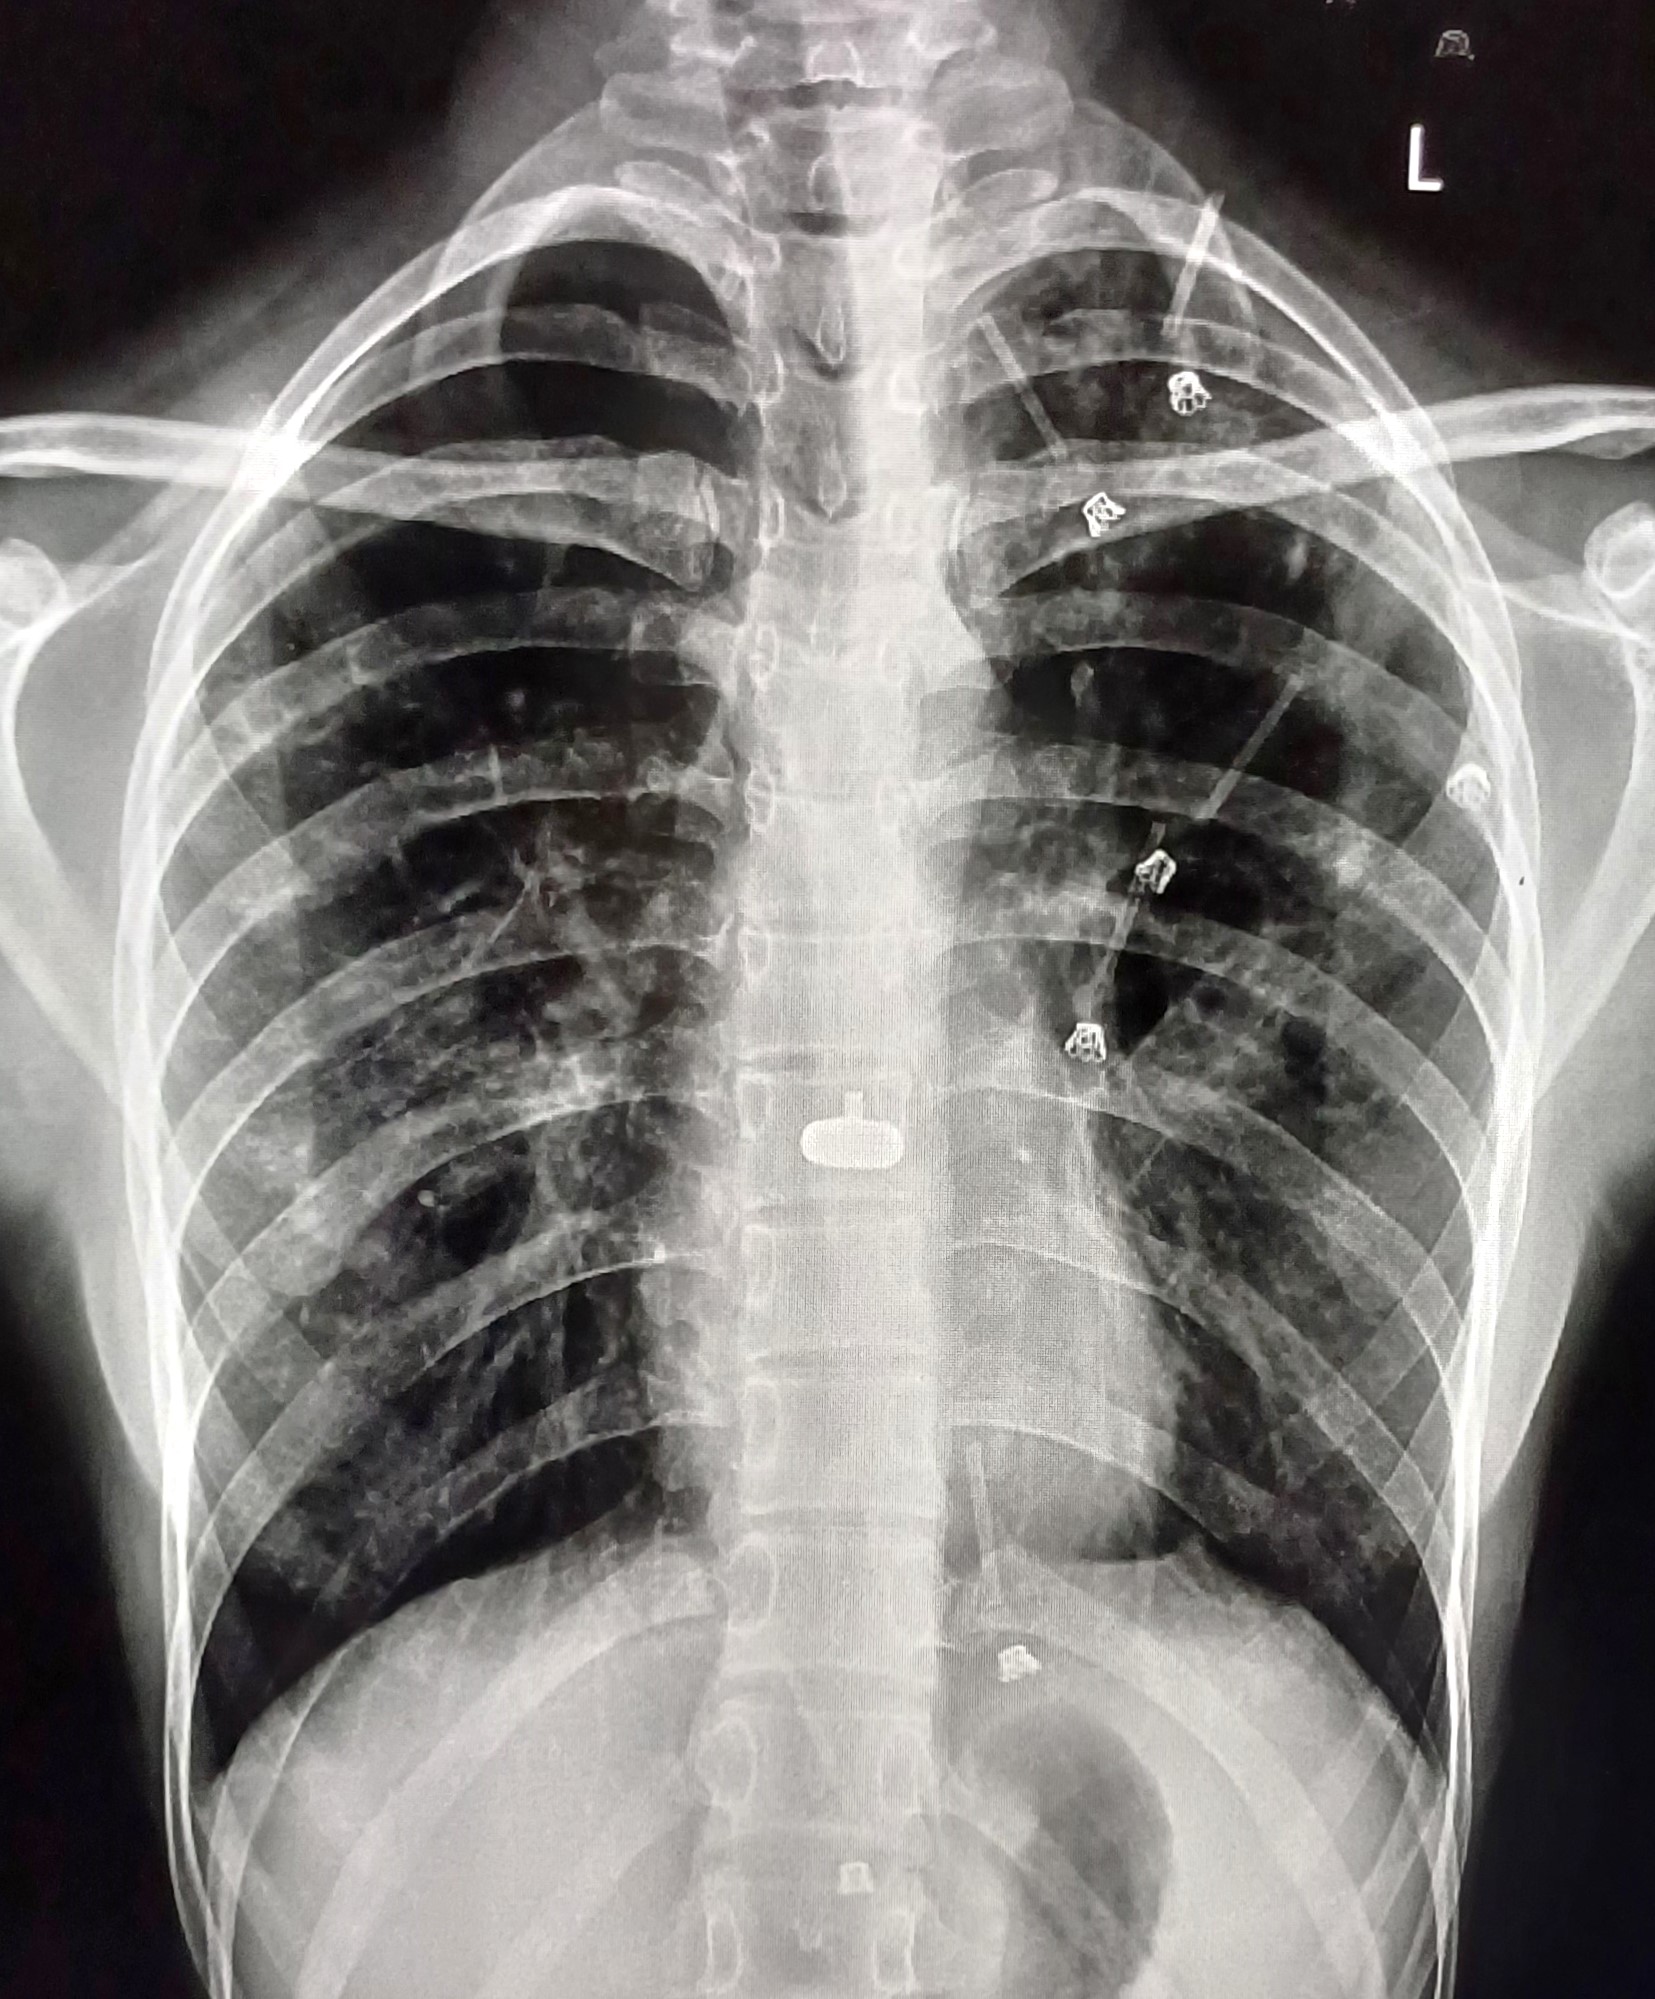

| 6 | IGGMC, Nagpur, Nagpur | P2 | 29-4466 | Hemrao Arambhe | Consent taken on Paper |

Provisional Diag : ?

Final Diag : interstitial lung disease |

Non-TB Case (Confirmed) | Right Lower zone mass lesion with bilateral hyperinflation with ILD in nodular in right lower zone | Abnormality visible on x-ray |

View |